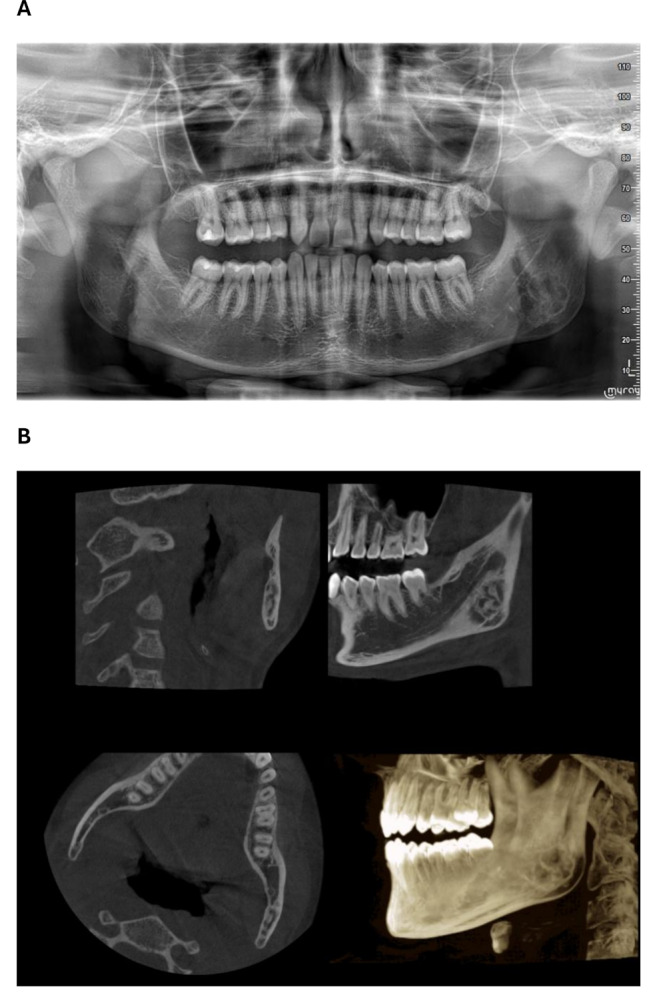

Xanthogranulomatous inflammation is a rare chronic inflammatory condition. It has been described in the long bones, and can affect various organs, including the salivary glands, gallbladder, kidneys, and gastrointestinal tract. The diagnosis is made throught histopathology which reveales foamy macrophages alongside polymorphonuclear leukocytes, plasma cells, and polyclonal lymphocytes arranged in a mosaic-like pattern. Here, we present the case of a 16-year-old boy in good general health who was referred by his orthodontist to the oral surgery department at Bretonneau Hospital for an asymptomatic multipartite image of the left mandibular angle that was discovered incidentally on a panoramic radiograph. The clinical examination was unremarkable. Cone beam computed tomography revealed a multipartite osteolytic lesion of the left mandibular angle, but this that was not specific enough for a diagnosis. Magnetic resonance imaging ruled out a vascular malformation. A biopsy revealed xanthogranulomatous osteomyelitis. In summary, this is the second case of xanthogranulomatous osteomyelitis localised to the mandible. This highlights a crucial point : radiological images of xanthogranulomatous osteomyelitis do not allow for a diagnosis; a biopsy is essential to rule out an aggressive or a malignant tumor.